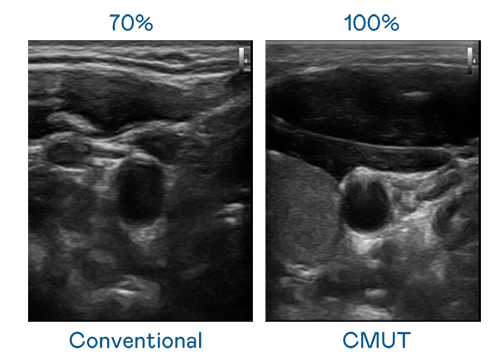

CMUT 技术是一种用电容式微机电元件来产生超音波讯号的技术。与传统 PZT 压电式技术相比,CMUT 频宽增加 30%,更宽频的超音波讯号让影像解析度大幅提升,是实现高影像品质医疗超音波扫描、促进精准医疗发展的关键技术。

大频宽带来超清晰影像

超音波影像的解析度高低,首先取决于探头能发出的讯号频宽。球速体育 CMUT 可提供高清晰的超音波讯号,提供高频宽、高灵敏度、影像纹理细节更高的超音波影像,协助医护人员缩短影像判读时间及利用精准的医疗影像进行诊断。